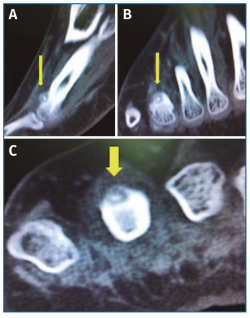

Con el objetivo de determinar las características de la lesión detectada en la RM, se indicó una gammagrafía ósea con tecnecio en 3 fases, que mostró un foco de hipercaptación de morfología redondeada en la cabeza del cuarto metatarsiano, compatible con una fractura de estrés (Figura 4). Una nueva RM en dispositivo convencional de 3T permitió detectar una lesión de 6 mm de diámetro en el dorso del cuello del cuarto metatarsiano, compatible con un osteoma osteoide (OO) (Figura 5). La TC de cortes finos a dicho nivel confirmó definitivamente la lesión tumoral (Figura 6).

Figura 6. Tomografía computarizada. A: corte sagital; B: corte coronal; C: corte axial. Imagen de la lesión radiolúcida, de contorno bien definido con punto central denso en dorso del 4.º metatarsiano, compatible con osteoma osteoide.